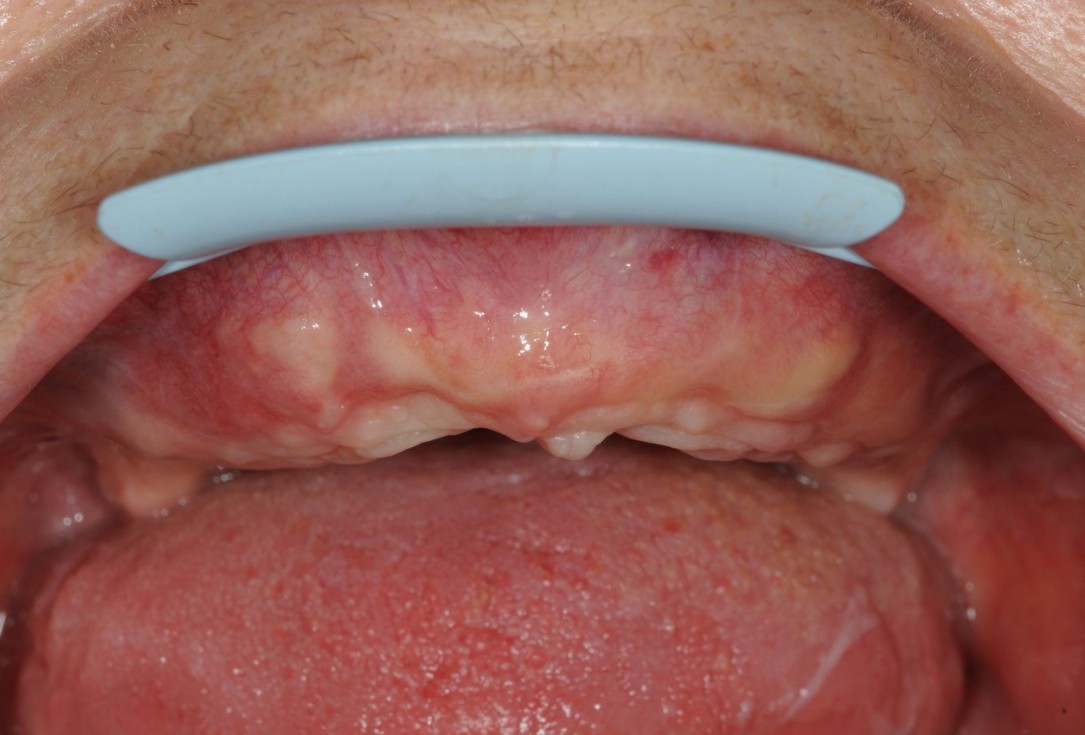

15/21 - 6 months post-op uneventful healing

16/21 - 6 months post-op uneventful healing / crestal view